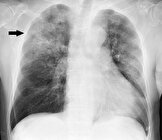

ذات الریه سالانه جان حدود ۲.۵ میلیون نفر را در جهان می‌گیرد

هر ساله در تاریخ ۱۲ نوامبر "روز جهانی ذات‌الریه" گرامی داشته می شود.